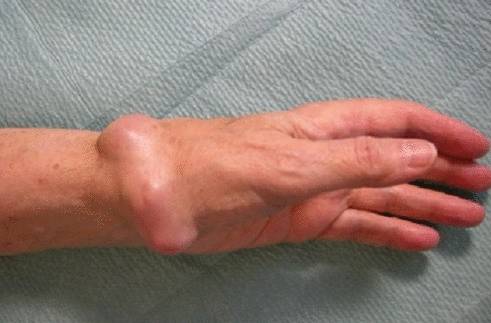

Остеома – фото:

Остеома кости – фото:

Остеома характеризуется костной выпуклостью, состоящей из пластинчатой ткани. Иногда могут присутствовать очаги фиброзно-костного поражения.

Под микроскопом остеомы имеют вид образований, покрытых снаружи тонким слоем волокнистой надкостницы. Цвет ‒ желто-белый, бугристый.

Как выглядит остеома? Это образование чаще всего является одиночным, имеет круглую или овальную форму, развивается из-под надкостницы или внутренней части, прилежащей к костномозговому каналу. Патологическое образование имеет твердую консистенцию.